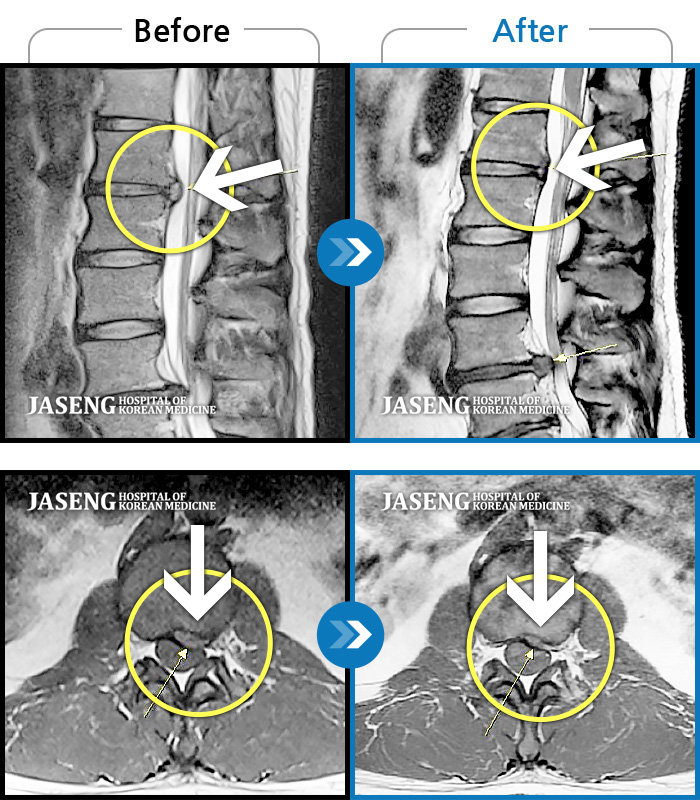

MRI 치료사례

양측 하요추부~좌측 골반부 통증, 좌측 하지 전반적 비증 및 족저부 간헐적 비증